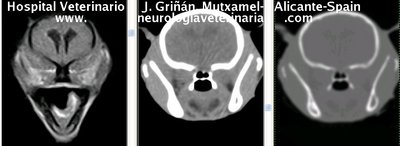

Se muestran cortes transversales de Resonancia Magnética (imagen a la izqda del lector), TC contrastado para tejidos blandos (imagen del centro) y TC contrastado para tejidos duros (imagen de la derecha del lector).

Nótese como la Resonancia supera al TC en el contraste de tejidos blandos (encéfalo y médula espinal) y en el de líquidos (ojo y líquido cefalorraquídeo), mientras que el TC supera a la resonancia en el contraste de tejidos duros (hueso) y aire (senos, cavidad nasal y bullas)

Cortes a nivel de los bulbos olfatorios